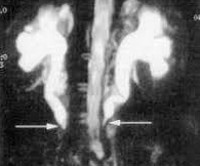

K66 Другие поражения брюшины